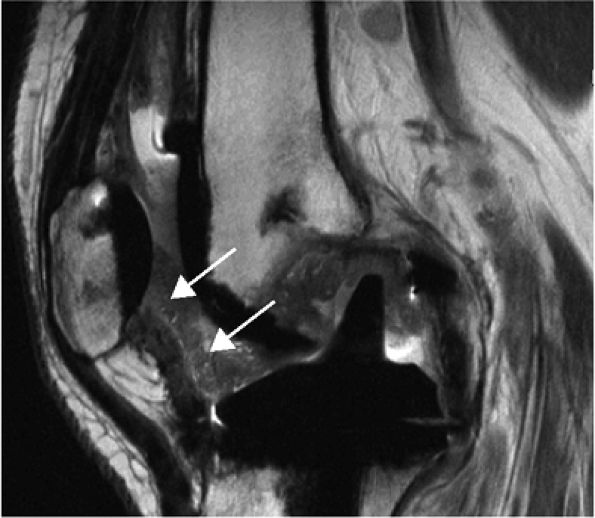

FIGURE 1.3 ● Total knee arthroplasty with synovitis (arrows). Acquired at 1.5 T. Use of an RBW of 83.3 kHz results in limited metallic susceptibility artifact.